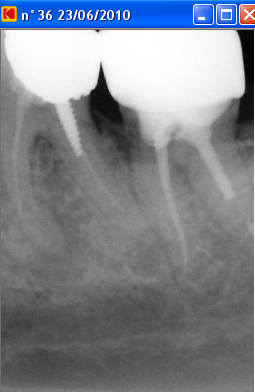

Un patient est venu pour la première fois en urgences pour douleur mandibulaire gauche: bilan radioclarté apicale sous la racine mésiale de 36, test percussion +++, ATB, disparition des douleurs à ce jour.

A la radio il y a une fausse route dans la racine mésiale.